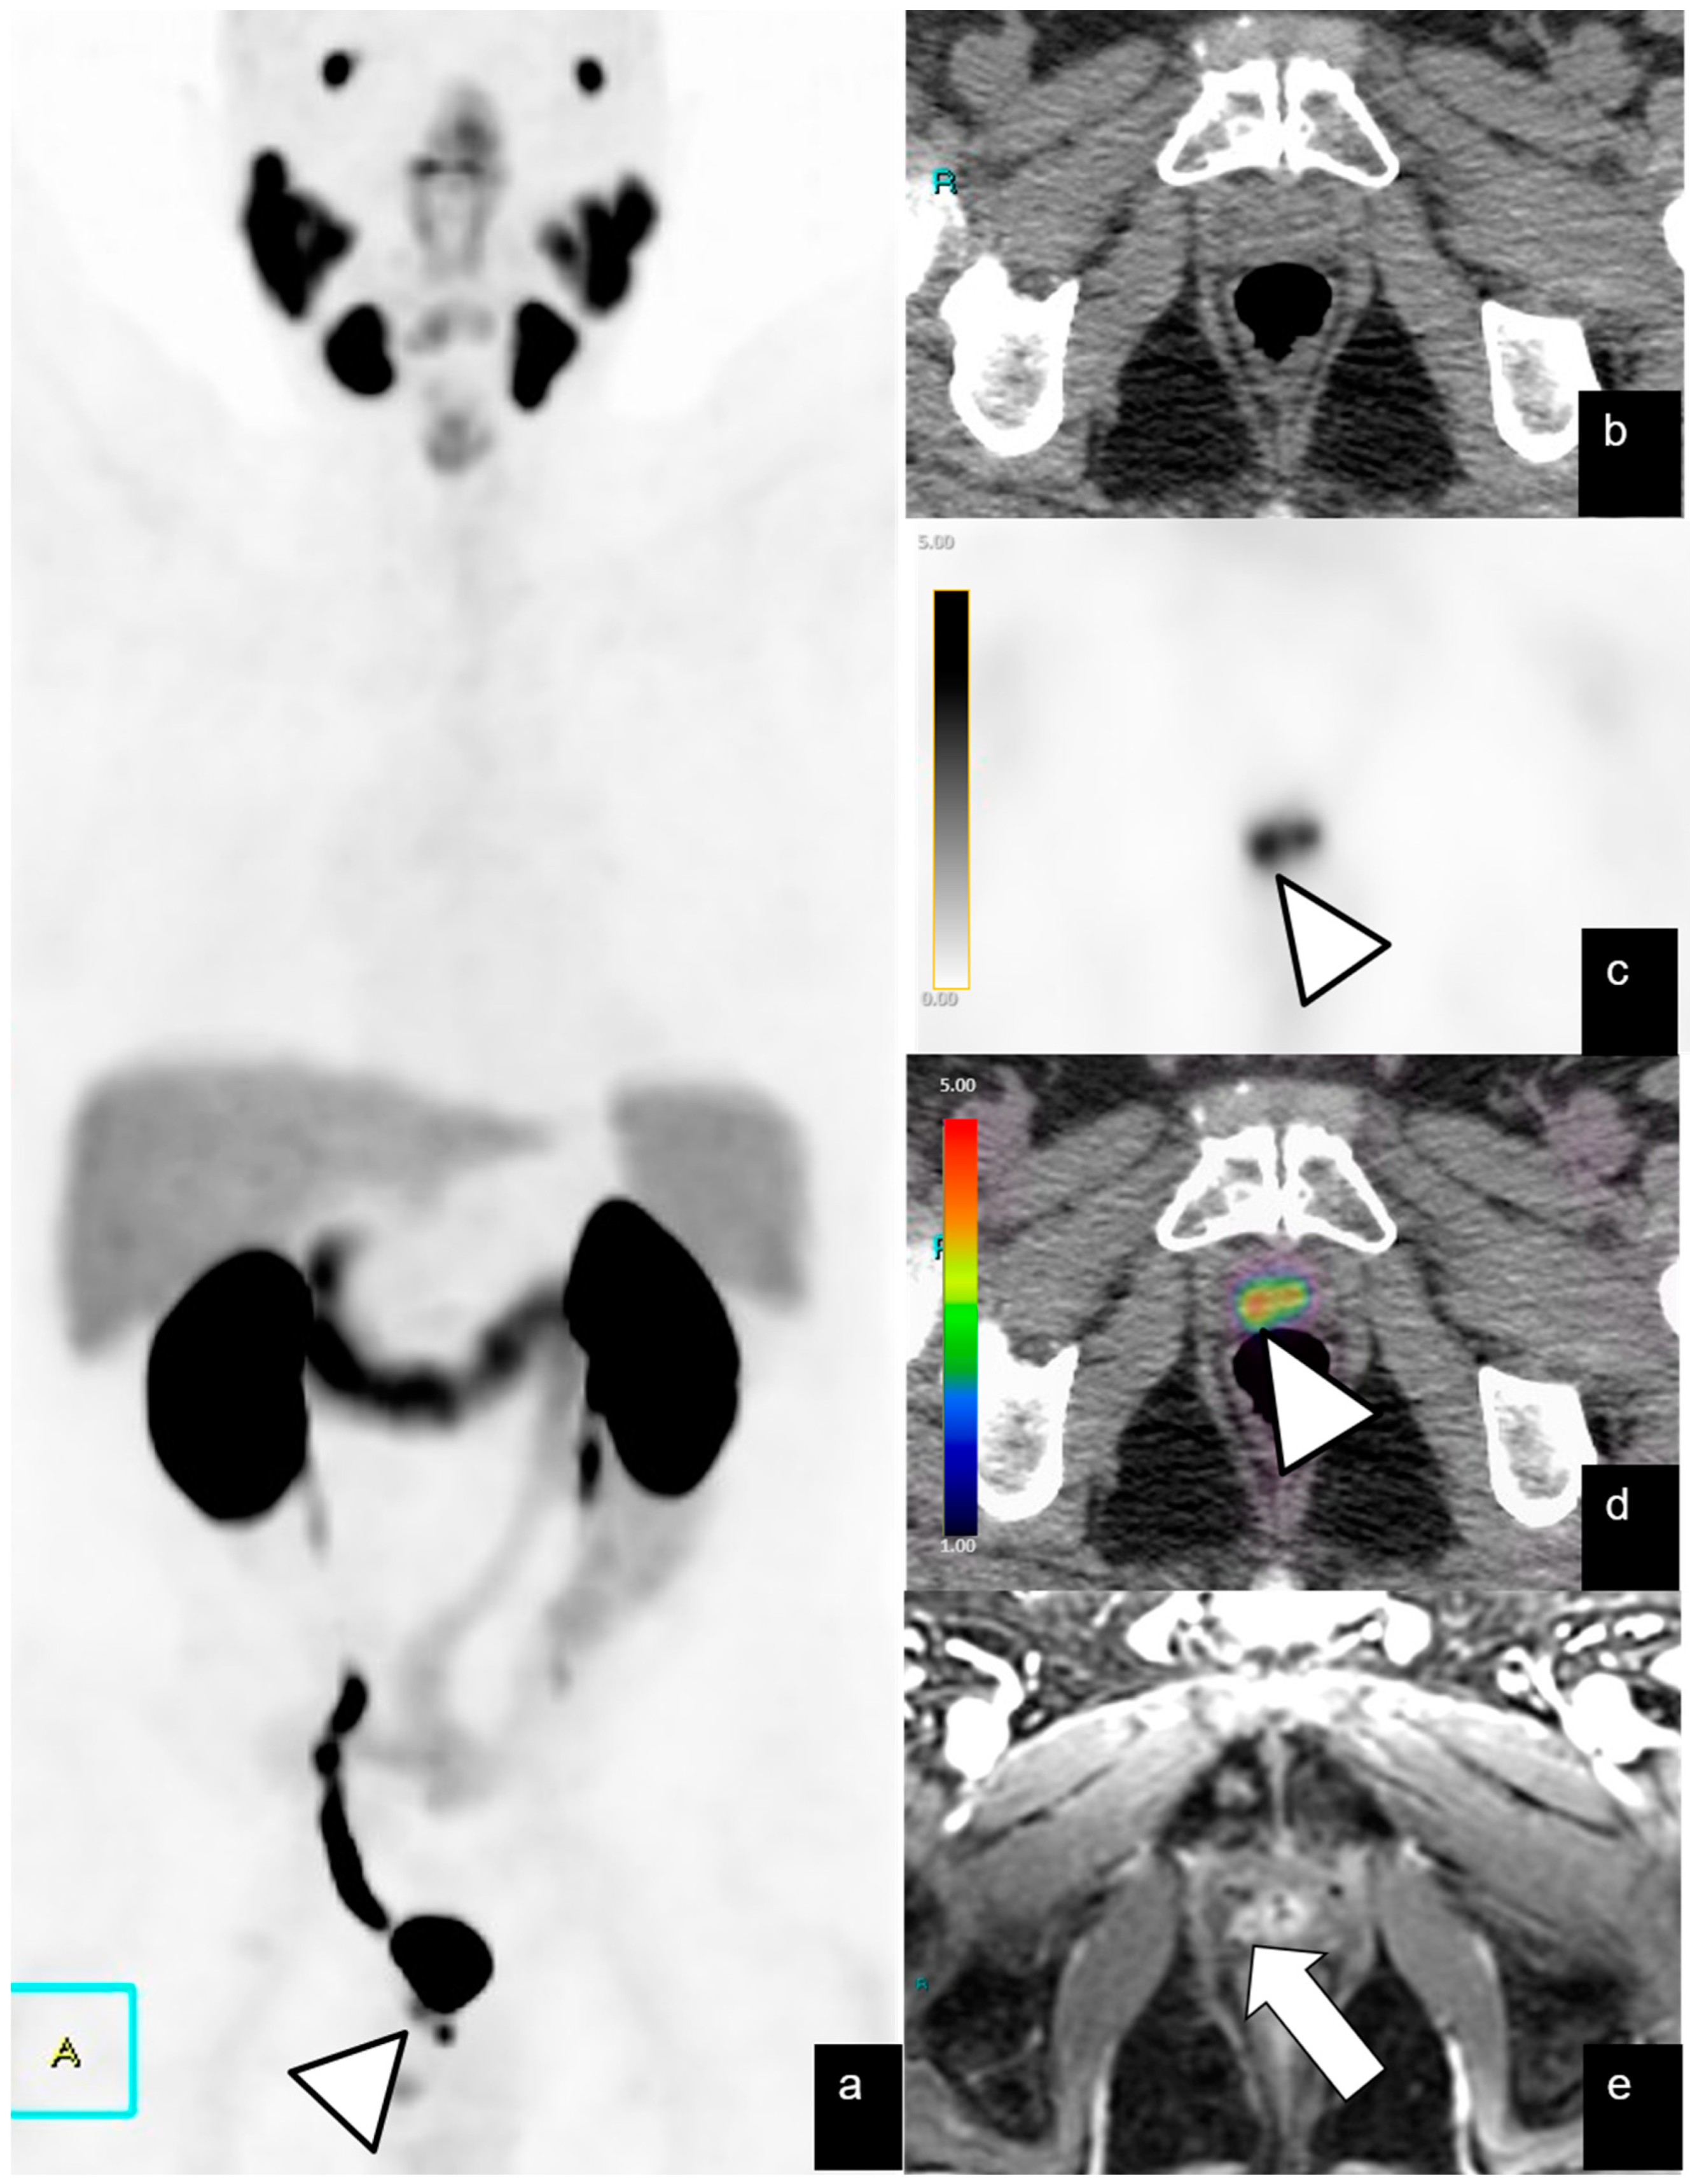

| Local recurrence | 42/128 (32%) | 12 | 2.1–46 | 9.6 | 3–53 |

| Lymph-node metastases | |||||

| Abdominopelvic | 39/128 (30%) | 24 | 1–73 | 7.3 | 2–19 |